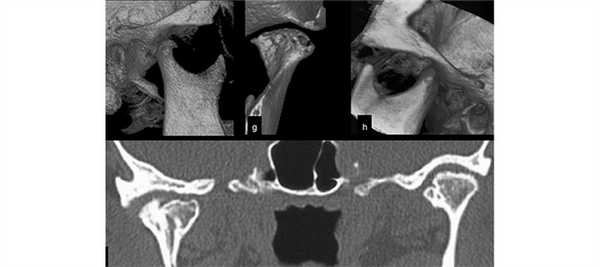

(Слева) На корональной КЛКТ ВНЧС (под углом) определяются пролиферативные дегенеративные изменения. Выраженность пролиферативного процесса может нарастать, что имитирует опухоль. Сделать заключение помогает конгруэнтность суставных поверхностей на фоне других признаков ДЗС и отсутствия объемного воздействия.

(Справа) На панорамной реформатированной КЛКТ определяется гиперплазия левого мыщелка. Кортикальные пластинки мыщелка и трабекулы субхондральной кости не изменены. Обратите внимание на дугообразное выбухание а шейки мыщелка и заднего края ветви.

(Слева) На панорамной рентгенограмме у пациента с переломом мыщелка определяется увеличение его размеров из-за наложения отломков.

(Справа) На сагиттальной КЛКТ у пациента с переломом левою мыщелка определяется его деформация и увеличение. Отломленный дефект сращен с ветвью, образуя «ступеньку». Определяется ре моделирование суставной ямки для приспособления к увеличенному мыщелку, а также ее уплощение и склерозирование. (Слева) На панорамной рентгенограмме определяется остеохондрома правого мыщелка. Мыщелок увеличен, ноипсилатеральная ветвь нижней челюсти не изменена, что позволяет исключить гиперплазию мыщелка.

(Справа) На панорамной рентгенограмме определяется остеохондрома левого мыщелка, отходящая от передней поверхности и сочленяющаяся с суставным возвышением, не позволяя мыщелку занимать суставную ямку. Трабекулярная кость опухоли продолжается в трабекулярную кость мыщелка. (Слева) На аксиальной КЛКТ определяется остеома ВНЧС, отходящая от заднего и внутреннего края мыщелка. Опухоль, образованная кортикальным и губчатым компонентами, возникает на периостальной поверхности мыщелка.

(Справа) На трехмерной реконструкции (вид сбоку) у этою же пациента визуализируется часть опухоли, отходящая от заднего края мыщелка и смещающая его кпереди.

(Слева) На корональной КЛКТ визуализируется расщепленный мыщелок с центральным вдавлением умеренной ширины и глубины, разделяющим мыщелок на наружную (большую) и внутреннюю (меньшую) доли. Мыщелок выглядит увеличенным и имеет форму «сердечка».

(Справа) На корональной КЛКТ определяется увеличение правого мыщелка, слившегося с височной костью за счет костного мостика ЕЭ с наружной стороны, а также облитерация суставного пространства. Шейка мыщелка и ветвь В нижней челюсти утолщены. (Слева) На кадрированной панорамной рентгенограмме определяется хондросаркома левого мыщелка. Мыщелок увеличен, опухоль рентгенонегативна, хорошо отграничена, мультифокальна.

(Справа) На аксиальной КТ в костном окне у этого же пациента определяется увеличение мыщелка с наличием рентгенонегативных включений, напоминающих пузырьки, с внутренней стороны. Нормальная трабекуляр ная картина отсутствует. Эти изменения позволяют отличить хондросаркому от гиперплазии мыщелка. (Слева) На аксиальной КТ в костном окне определяется остеосаркома левого мыщелка, проявляющаяся тотальным его увеличением с деструкцией трабекулярной костив Кортикальная пластинка мыщелка истончена и деформирована.

(Справа) На аксиальной КТ в костном окне определяется остеосаркома ветви и мыщелка нижней челюсти справа. Мыщелок увеличен, ветвь утолщена за счет спикулообразной периостальной реакции, типичной для остеосаркомы. Снаружи от нижней челюсти определяется сопутствующая мягкотканная опухоль.